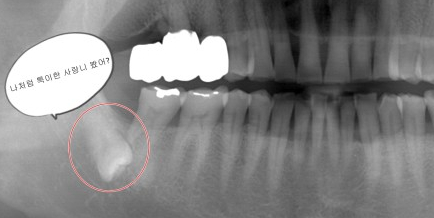

- 사랑니와 옆에 있는 치아에 충치가 있는 경우

관리하기가 어려운 사랑니는 잇몸뿐 아니라 치아 자체에도 충치를 유발합니다.

사랑니를 아무 탈 없이 건강하게 유지하는 것은 정말 어려운 일입니다.